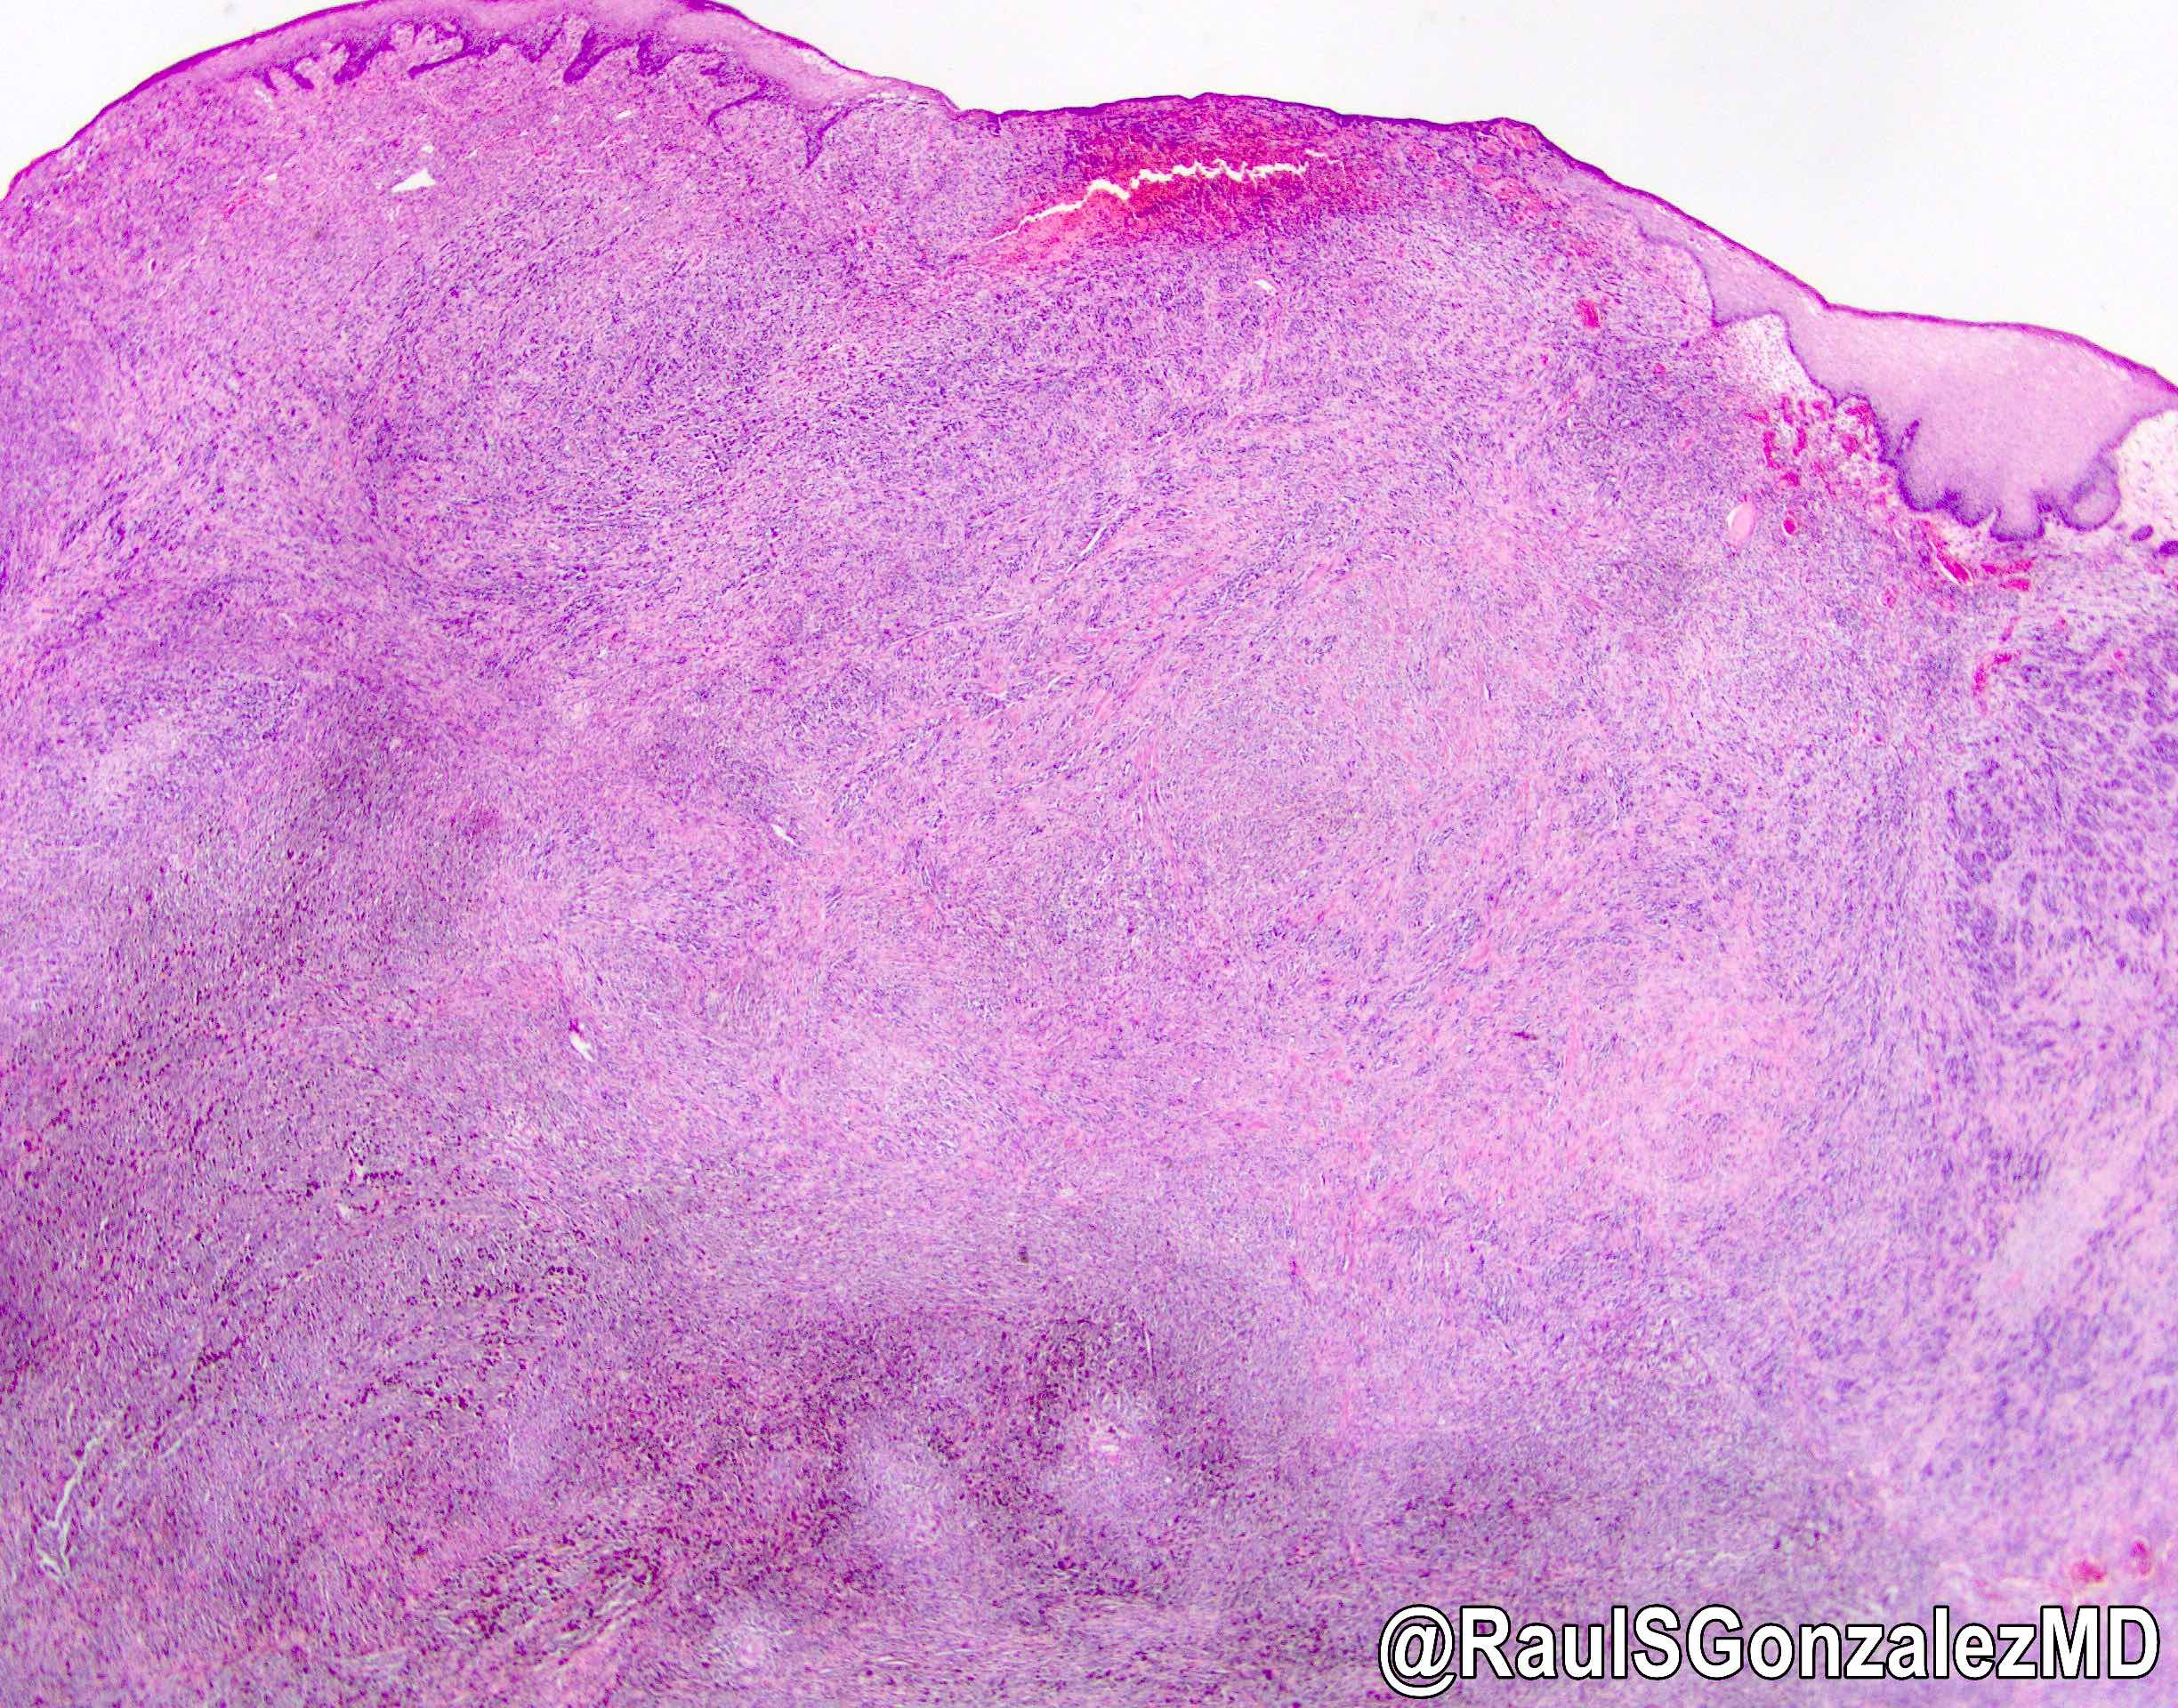

- Associated melanoma in situ component (junctional melanocytic activity / junctional melanocytic component / tumor nests at the epithelium - lamina propria junction / horizontal tumor spread in the basal layer of the epithelium) and melanocytosis / melanosis (Mod Pathol 2019;32:957, Ann Thorac Surg 2013;96:1002)

A. Junctional melanocytic activity (shown in the picture) suggests a primary malignant melanoma of the esophagus